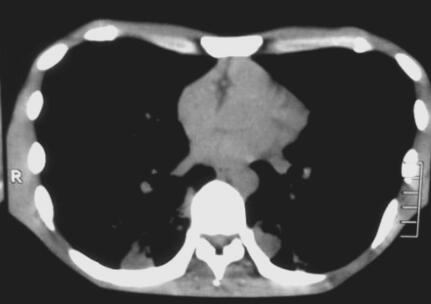

给予糖皮质激素(甲泼尼龙)40mg/d,静脉点滴,2周后逐渐减量,持续3个月,并辅以机械排痰、拍背、体位引流及加强营养等对症处理。治疗1周后患者精神状态明显好转,咳嗽、咳痰症状减轻,发热症状消失。2014年1月27日我院门诊复查胸部CT(图2)对比2013年11月15日CT可见双下肺病灶吸收明显,病灶周围可见高密度小结节影及纤维条索影。

图2 2014年1月27日复查胸部CT

患者双下肺斑片影明显吸收消散